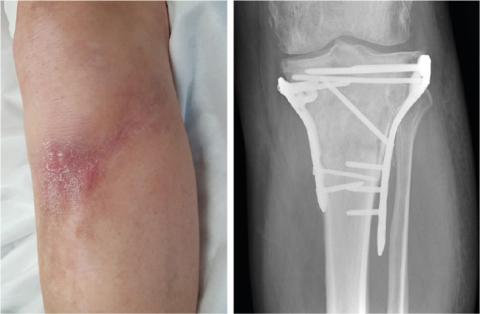

Tremånederskontrol efter operation med skinne og skruer for en proksimal tibiafraktur. Klinisk rødme og hævelse af cikatricen og radiologisk osteolytiske forandringer ved den laterale skinne. Ingen af fundene er bekræftende for en frakturrelateret infektion.